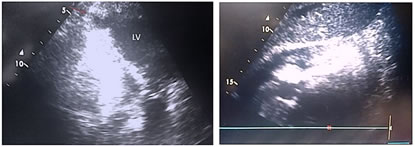

A 70-year-old hypertensive female, presented with sudden onset of chest pain and vomiting. Her ECG revealed ST segment elevation in V1-V4 with left bundle branch block. Transthoracicecho cardiogram showed rupture of LV anterior free wall with ejection fraction of a round 30% and akineticanterior segments(Fig 1 and 2).

Figure 1                                                   Figure 2

Figure 1: Transthoracic echocardiography apical four chamber view showing rent in anterior wall; Figure 2: Transthoracic echocardiography subcostal view showing significant pericardial effusion; Figure 3: Surgical image showing anterior LV free wall rupture; Figure 4: Diagram depicting surgical patch closure of LV free wall rupture